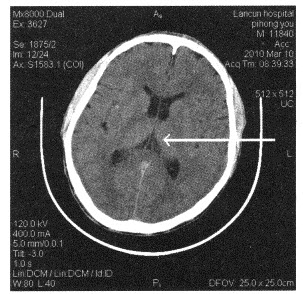

患者,男性,50岁。突发昏迷2小时。既往有高血压病史。

第1题,共1个问题

(单选题)该患者最可能诊断为()

A:脑星形细胞瘤

B:脑出血

C:脑转移瘤

D:动脉瘤

E:脑脓肿

下面颅脑断层图像中箭头所指为()

A:尾状核

B:屏状核

C:内囊后肢

D:背侧丘脑

E:豆状核